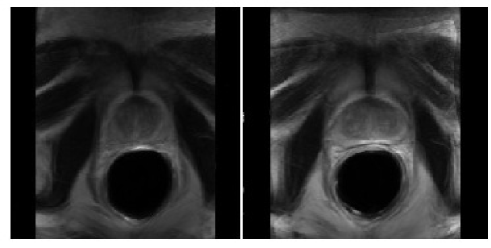

Figure 3: Example of atlas generated using only intensity information (left) and using intensity and geometric information (right)

Refer to caption

Very often, anatomical atlas construction only makes use of intensity information to estimate the transformation to the reference. However, such methods are not usable in our case because of too important mismatches which may appear between reference segmentation and deformed template segmentation. The construction of an atlas using this method gives poor results. To address this problem we use the hybrid method introduced in section 4.1. The geometric criterion (ICP) works on the contours given by the expert segmentations while the intensity based criterion (SSD) works on the images using a SSD as a similarity measure. The matching problem is then solved using an ICP criterion (“hard assignment”): for each scene points sjsubscript𝑠𝑗s_{j}, wij=1subscript𝑤𝑖𝑗1w_{ij}=1 if misubscript𝑚𝑖m_{i} is the closest model point of sjsubscript𝑠𝑗s_{j} else wij=0subscript𝑤𝑖𝑗0w_{ij}=0.